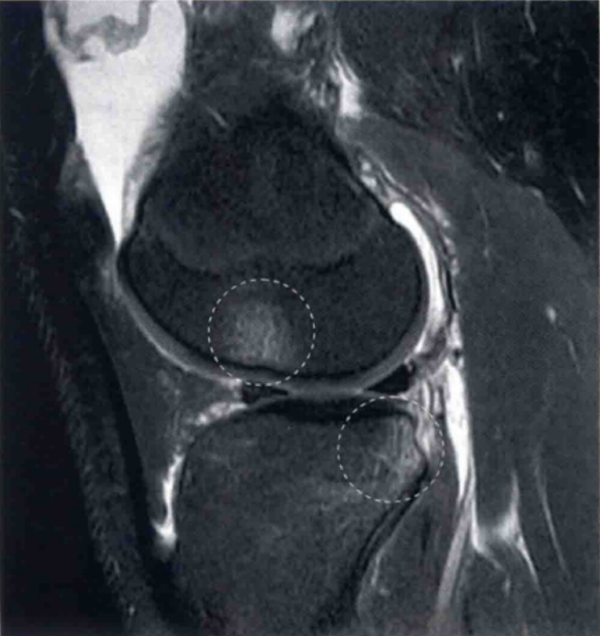

图3 a和b显示的为冠状位质子加权像和轴位T2像,并在关节镜下证明了为ACL股骨端撕裂。

在a中ACL股骨止点的信号增强,并且不能看到切带附着点(圆形区)。在b中ACL股骨附着点缺失(圆形区)。将图3b与图1b对比观察可显示正常的股骨止点